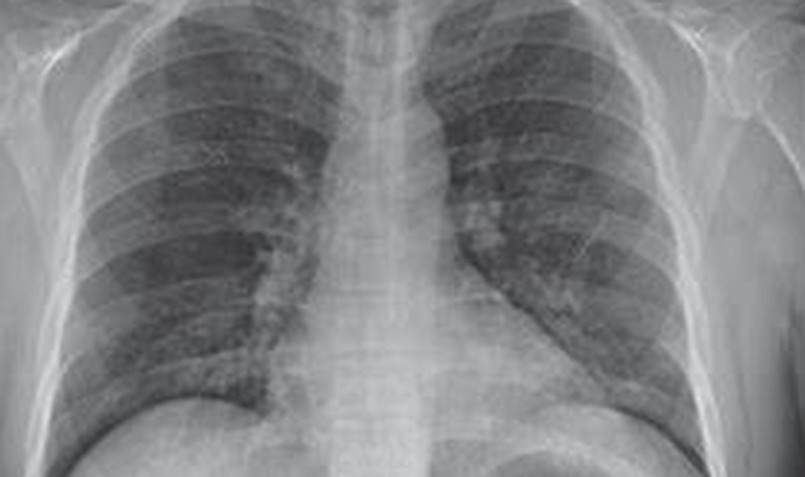

| Hình ảnh "phổi trắng" trên phim X-quang. |

Một bệnh nhân nam 59 tuổi bị suy hô hấp nặng, phổi mất chức năng thông khí, hôn mê do biến chứng cúm A và phải can thiệp ECMO. Bác sĩ cho biết phổi của ông đã bị tổn thương tới 90%, dẫn đến sốc nhiễm khuẩn nghiêm trọng, làm CO2 tích tụ trong máu, gây tình trạng "phổi trắng".

Trường hợp khác, một bệnh nhân 66 tuổi có tiền sử bệnh phổi tắc nghẽn mạn tính, phải phụ thuộc hoàn toàn vào máy thở. Ban đầu, ông nhập viện với các triệu chứng giống cảm cúm thông thường như sốt, ho, khó thở. Tuy nhiên, chỉ sau hai ngày, tình trạng diễn tiến nghiêm trọng, phổi bị tổn thương 50-60%, trắng xóa trên phim X-quang.

Tiến sĩ - bác sĩ Bùi Phạm Minh Mẫn, Bệnh viện Đại học Y Dược TP.HCM - cơ sở 3, cho biết "phổi trắng" là thuật ngữ y khoa dùng để mô tả hình ảnh X-quang hoặc CT scan của phổi bị tổn thương nghiêm trọng, xuất hiện dưới dạng vùng trắng mờ do dịch viêm tích tụ. Hiện tượng này thường gặp ở những bệnh nhân nhiễm cúm nặng, đặc biệt do virus cúm A/H5N1, cúm A/H1N1 hoặc cúm B gây biến chứng.

Theo các chuyên gia hô hấp, tình trạng "phổi trắng" khi nhiễm cúm thường là hậu quả của hội chứng suy hô hấp cấp tính (ARDS) – một biến chứng nghiêm trọng do phản ứng viêm quá mức của cơ thể trước sự tấn công của virus. Khi virus cúm xâm nhập, hệ miễn dịch phản ứng mạnh mẽ, làm tổn thương hàng rào phế nang - mao mạch, khiến dịch viêm tràn vào phế nang, làm suy giảm nghiêm trọng khả năng trao đổi khí của phổi.

| Tình trạng "phổi trắng" khi nhiễm cúm thường là hậu quả của hội chứng suy hô hấp. |